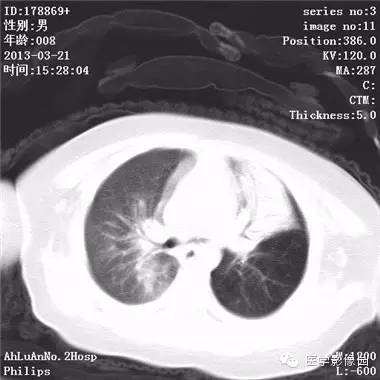

患儿男,8个月,呛咳,发热一周。实验室检查白细胞及中性粒细胞增高。

两肺肺纹理增多、增粗,右肺可见斑片状、片絮状模糊影,边界欠清;左肺上叶见楔形高密度影,内可见支气管征,尖端指向肺门;左肺下叶肺野透亮度增强;另见左肺主支气管内可见块状软组织密度影。

支气管异物(花生米)伴两肺炎症(追问病史,患儿奶奶层于一周前喂食患儿花生米,当时疑似“呛进去”,后来见好了也就没留意)。